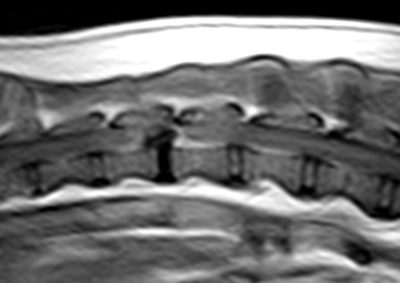

脳神経外科 注意 ボタンをクリックした先に、治療中および手術中の画像が説明で使用されている場合がございます。 そのような画像に弱い方は閲覧なさらないようお願いいたします。 脳神経外科 Ventral Slot 脳神経外科 椎間板ヘルニア 脳神経外科 PLDD 多発性頸部椎間板ヘルニア 脳神経外科 椎間板ヘルニア 脳神経外科 経皮的レーザー椎間板除圧術 PLDD 脳神経外科 椎間板ヘルニア 脳神経外科 環軸椎不安定症に対する環軸固定術 脳神経外科リハビリテーション… 脊髄梗塞 脳神経外科 ベントラルスロット 脳神経外科 ベントラルスロット 脳神経外科 環軸不安定症 脳神経外科内科 Feline Meningoencephalomyelitis of Unknown Origin : 猫の... <1234567> 症例カテゴリー 放射線治療整形外科軟部組織外科脳神経外科内科腫瘍外科救急・集中治療リハビリテーション科腫瘍内科内視鏡科脳神経科呼吸器外科中医・漢方猫の腎移植循環器科